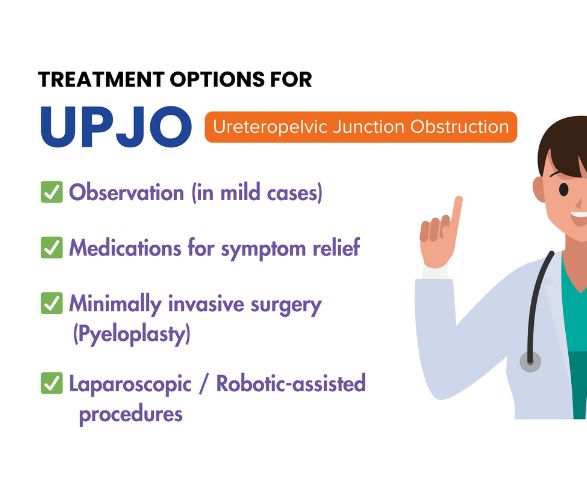

Treatment Options for UPJ Obstruction

✅ Observation & Monitoring – Mild or asymptomatic cases may be managed with regular follow-up scans to monitor kidney function and drainage.

✅ Endopyelotomy – A minimally invasive endoscopic procedure where the narrowed junction is incised to improve urine flow.

✅ Pyeloplasty (Laparoscopic/Robotic/Open) – The gold-standard surgical treatment that removes the blocked segment and reconstructs the ureter for long-term relief.

✅ Temporary Stenting or Nephrostomy – Used to immediately relieve obstruction and drain urine while preparing for definitive treatment.

✅ Medical Management – Antibiotics and pain control may be used to treat infections or symptoms associated with UPJ obstruction.